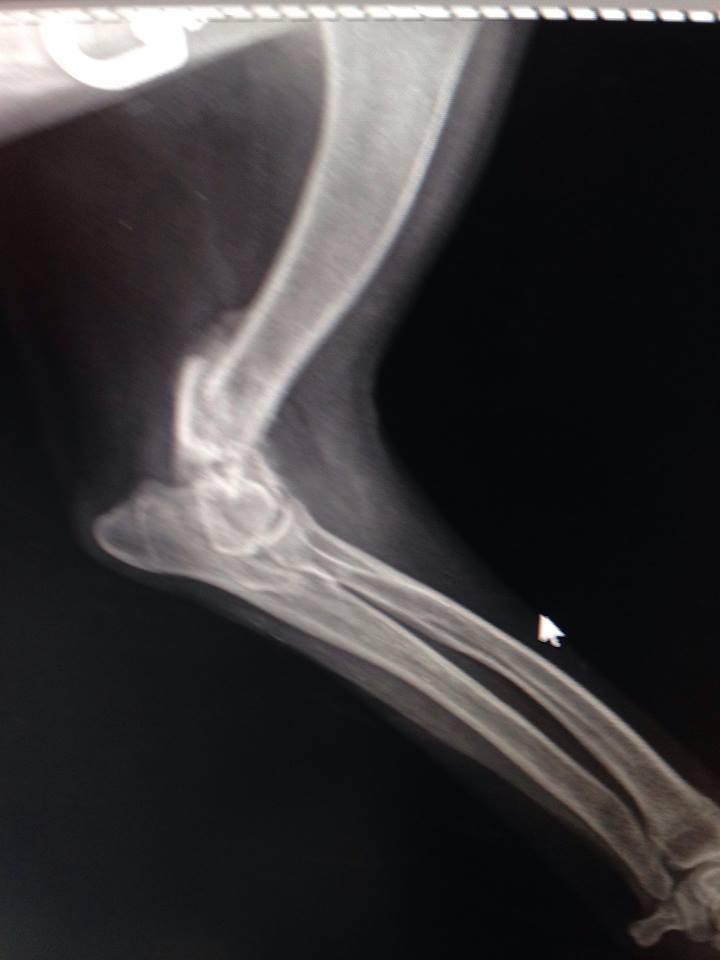

Надо мелкой рентген срочно делать

На лапу не наступает.... гипс не помню сколько был, но возможно, не правильно сложили

Вобщем все гораздо хуже оказалось.Только характер приятный,ласкавая.

Очень паршивый перелом.... сложная операция.

Не понятно куда и зачем одевали гипс.... зато стерилизовали.

Да,так и есть.Пишу посты,кидаю в личку-дорого обходятся чужие ошибки.Самое обидное,что если бы сразу сделали,то даже не хромала бы и цена была бы совсем другая.